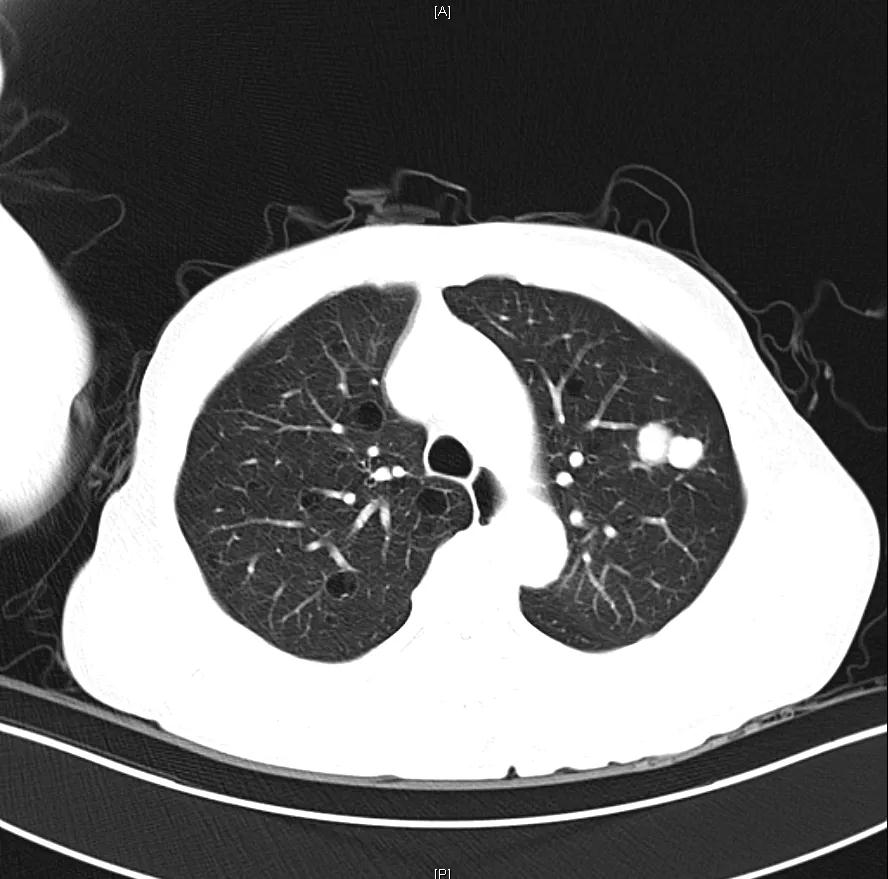

Δ肺CT:双肺多发转移

肝脏弹性超声:12kPa。腹部MRI平扫+增强:肝巨块结节性HCC(最大径18.4cm)伴肝内多发转移(最大径3.5cm),肝右静脉广泛癌栓形成;肝硬化伴门脉高压、脾大、少量腹水;肝囊肿;双肺多发转移。胸部CT平扫:两肺多发转移,两肺气肿伴肺大泡,两肺散在慢性炎症,右侧少量胸水。